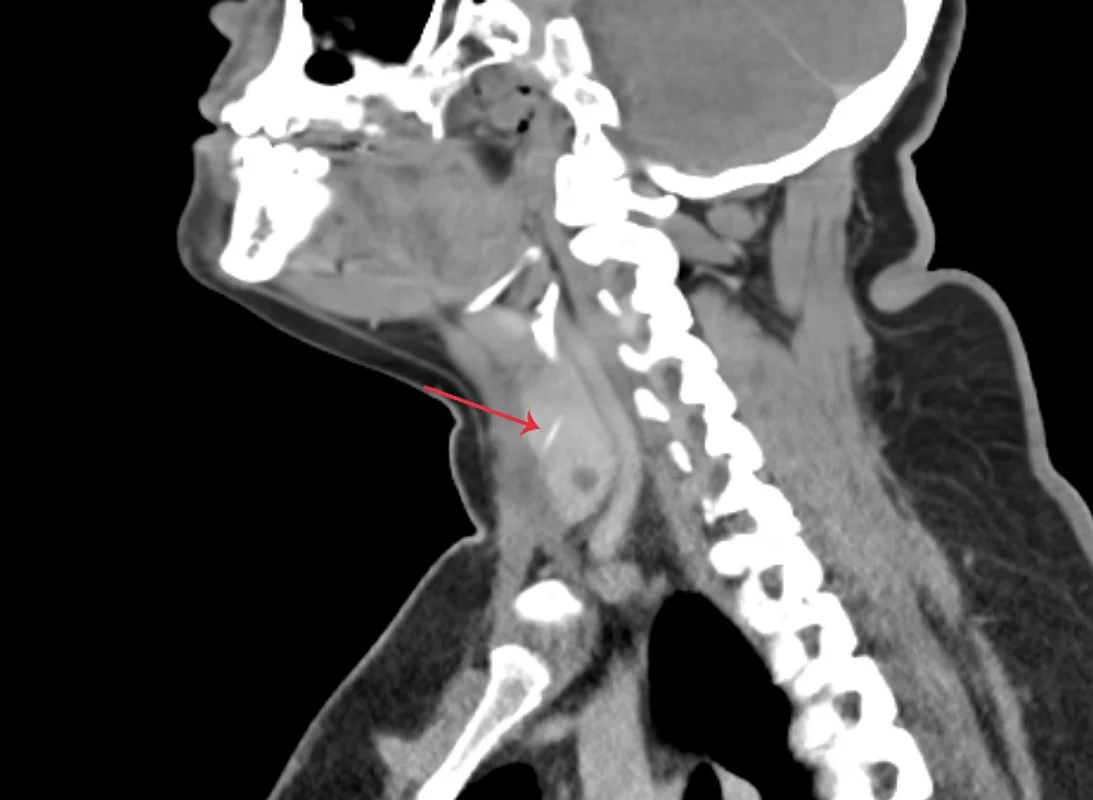

Doctors found that the 3cm long bone had travelled down from her throat and lodged in her thyroid gland

The doctors found that the 3cm long bone had travelled down from her throat and lodged in her thyroid gland- something that could have life-threatening consequences. It was then surgically removed by a team of doctors from Aster Hospital Mankhool.

At the hospital, the patient underwent a CT scan which confirmed the presence of a 3cm bone embedded in the right thyroid lobe, penetrating the strap muscle. A surgical intervention was conducted under general anaesthesia, during which the bone was successfully extracted, and the wound meticulously closed.